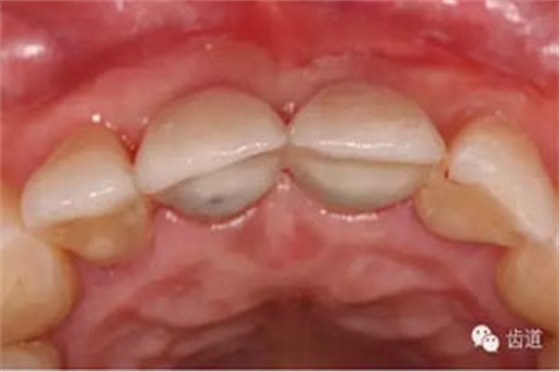

合面觀